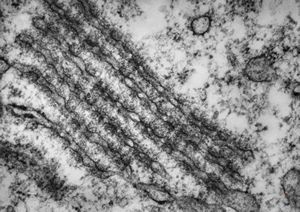

M,26y. | ribosome-lamella bodies in adenocarcinoma

M,41y. | ribosome-lamella complex in tricholeukocyte -hairy cell leukemia, spleen